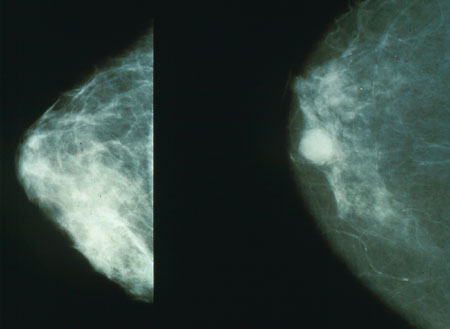

Gesunde Brust (links) und Mammakarzinom (rechts)